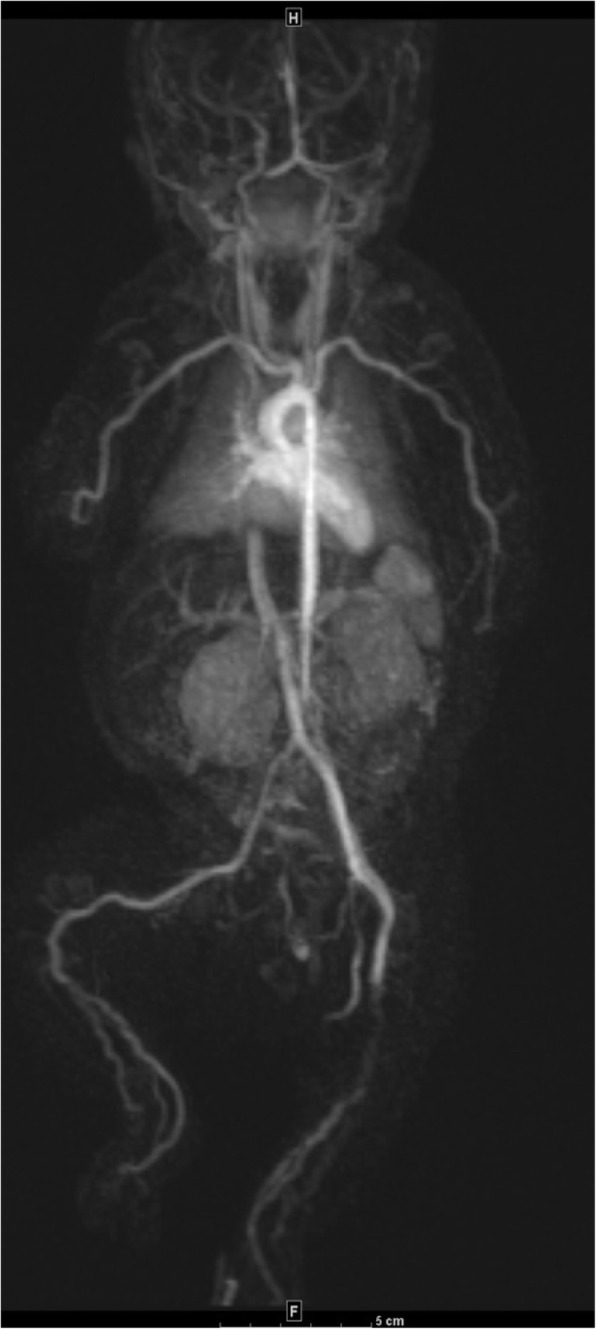

Full body magnetic resonance angiography (MRA) was significant for abnormalities in the upper limbs with tortuosity and gadolinium enhancement of the brachial as well as the distal axillary arteries. In the lower limbs, tortuosities and gadolinium enhancement involving distal femoral, popliteal, posterior and anterior tibialis arteries suggestive of vasculitis or vasculopathy (Fig. 2). Aortic, pulmonary, renal and celiac trunk vessels were normal. Given the clinical syndrome, imaging findings and response to corticosteroid administration, vasculitis was favored.

Fig. 2.

Magnetic resonance angiography at one month of age. Gadolinium enhancing irregular and tortuous appearing medium sized arteries bilaterally in the upper and lower extremities